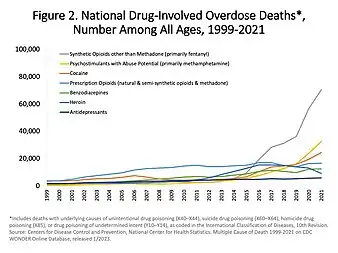

Methamphetamine overdose is a diverse term. It frequently refers to the exaggeration of the unusual effects with features such as irritability, agitation, hallucinations and paranoia. It might also refer to intentional self-harm or a fatal outcome. The CDC reported that the number of deaths in the United States involving psychostimulants with abuse potential to be 23,837 in 2020 and 32,537 in 2021.[107] This category code (ICD–10 of T43.6) includes primarily methamphetamine but also other stimulants such as amphetamine, and methylphenidate. The mechanism of death in these cases is not reported in these statistics and is difficult to know.[108] Some deaths are as a result of intracranial hemorrhage[109] and some deaths are cardiovascular in nature including flash pulmonary edema[110] and ventricular fibrillation.[111]